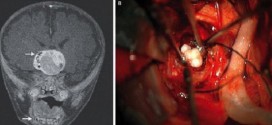

Rare Tumor Removed From Baby Had Teeth (Photo)

Rare Tumor Removed From Baby Had Teeth

A 4-month-old male infant in Maryland is probably the first person to have had teeth form in his brain. The teeth were formed as a result of a rare brain tumor, according to a news report. The tumor has been removed from the brain and doctors confirm that the infant’s condition is stable. At the beginning, doctors suspected something unnatural …